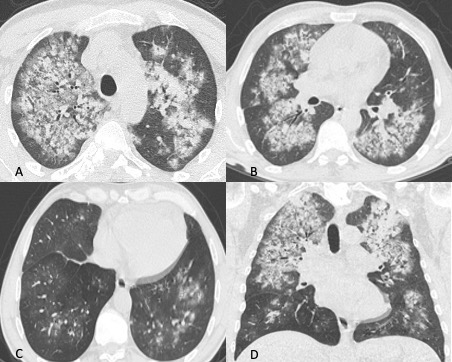

Figura 4: Donna di 78 anni con diagnosi di Linfoma di Hodgkin. Le immagini assiali (A-B-C) mostrano il parenchima polmonare normale. Un anno dopo la paziente giunge al Pronto Soccorso per un rapido peggioramento della funzionalità respiratoria, dispnea e tosse. La TCAR eseguita alcuni giorni dopo il ricovero nel reparto di Malattie Infettive (D-E-F) mostra la presenza in entrambi i polmoni di "vetro smerigliato" diffuso con relativo risparmio delle zone sub-pleuriche e la comparsa di formazioni pseudocistiche nel lobo superiore sinistro (frecce in D ed E). L’ipotesi formulata e poi confermata dal laboratorio è stata quella di polmonite da Pneumocystis Jirovecii.

Figura 5: Uomo di 68 anni immunocompromesso giunge al Pronto Soccorso per IRA. La TCAR eseguita all’ingresso (immagini assiali A-B-C e la ricostruzione MPR sul piano coronale D) mostrano "vetro smerigliato" diffuso e simmetrico in entrambi i polmoni con relativo risparmio delle aree sub-pleuriche solo in alcune zone nel polmone. L’ipotesi diagnostica formulata è stata quella di polmonite interstiziale. Le indagini di laboratorio hanno in seguito rivelato che l’agente patogeno responsabile del quadro flogistico era lo Pneumocystis Jirovecii. La diagnosi differenziale tra le varie cause di iperdensità parenchimale nei pazienti con IRA non è semplice soprattutto quando le alterazioni sono molto estese e diffuse.

I reperti TCAR sono diversi, in genere nella fase iniziale si documenta la presenza di “vetro smerigliato” diffuso a distribuzione simmetrica che in alcuni casi mostra prevalente distribuzione perilare con risparmio delle zone sub pleuriche e predilezione per i lobi superiori. In seguito, si sovrappongono ispessimento dei setti interlobulari (“crazy paving” pattern), aree di consolidazione parenchimale, noduli e formazione di pseudocisti sub pleuriche (non sempre presenti) che possono andare incontro a rottura provocando pneumotorace spontaneo (Figure 4 e 5).

La diagnosi differenziale con la polmonite da SARS-CoV-2 non è dunque semplice, ciò che può aiutare il radiologo è la clinica (paziente immunocompetente o immunocompromesso), la distribuzione prevalentemente peri ilare delle aree di iperdensità ed i reperti associati sopradescritti.